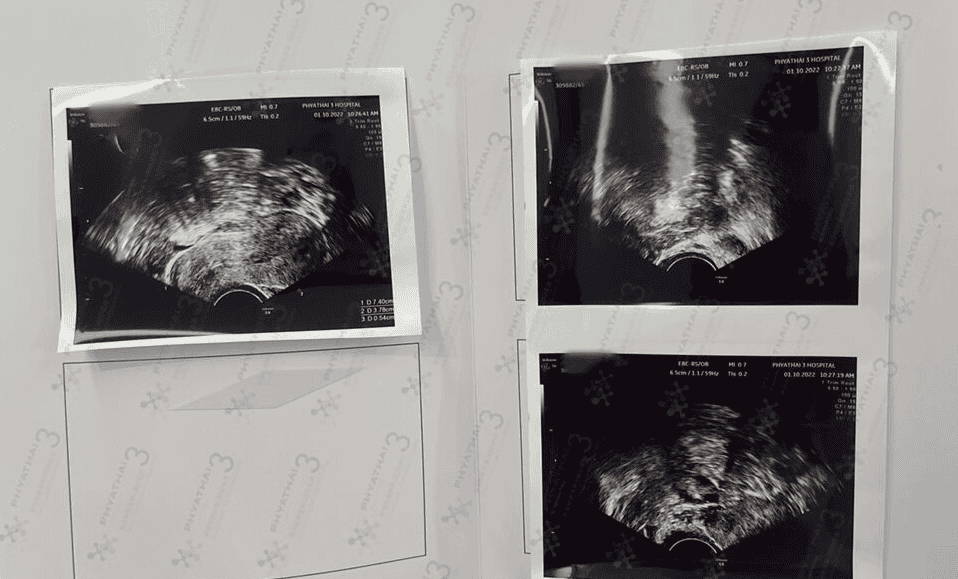

首先,胎停是胚胎发育到一个阶段发生了死亡而停止继续发育的现象,通过B超检查表现为妊娠囊内胎芽或胎儿形态不整,无胎心搏动,或表现为妊娠囊枯萎,这些均属于胎停的范畴,所以我们需要做好以下几点。